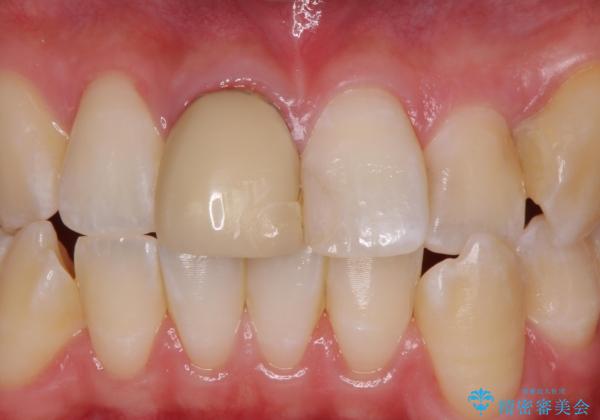

色・形ともに改善され、大変喜んでいただけました。

- 右上1: 仮歯/11,000円、ジルコニアクラウン(スタンダード)/121,000円 合計132,000円(税込)費用は治療当時の料金となります